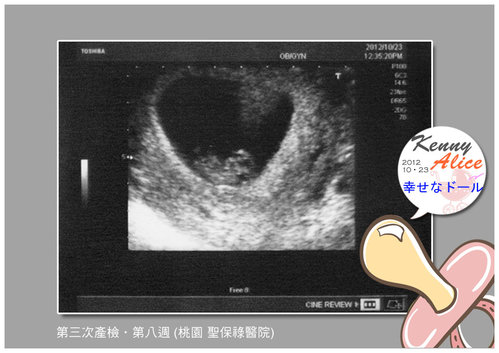

有了 有了這張些許有點清楚一點囉!!

楊醫生說..黑色的地方就是媽媽替小B寶準備的小套房~哈哈..這比喻還真有趣!!

小B寶呀!! 你有沒有看到,媽咪替你準備的小套房有愛心的形狀耶!!